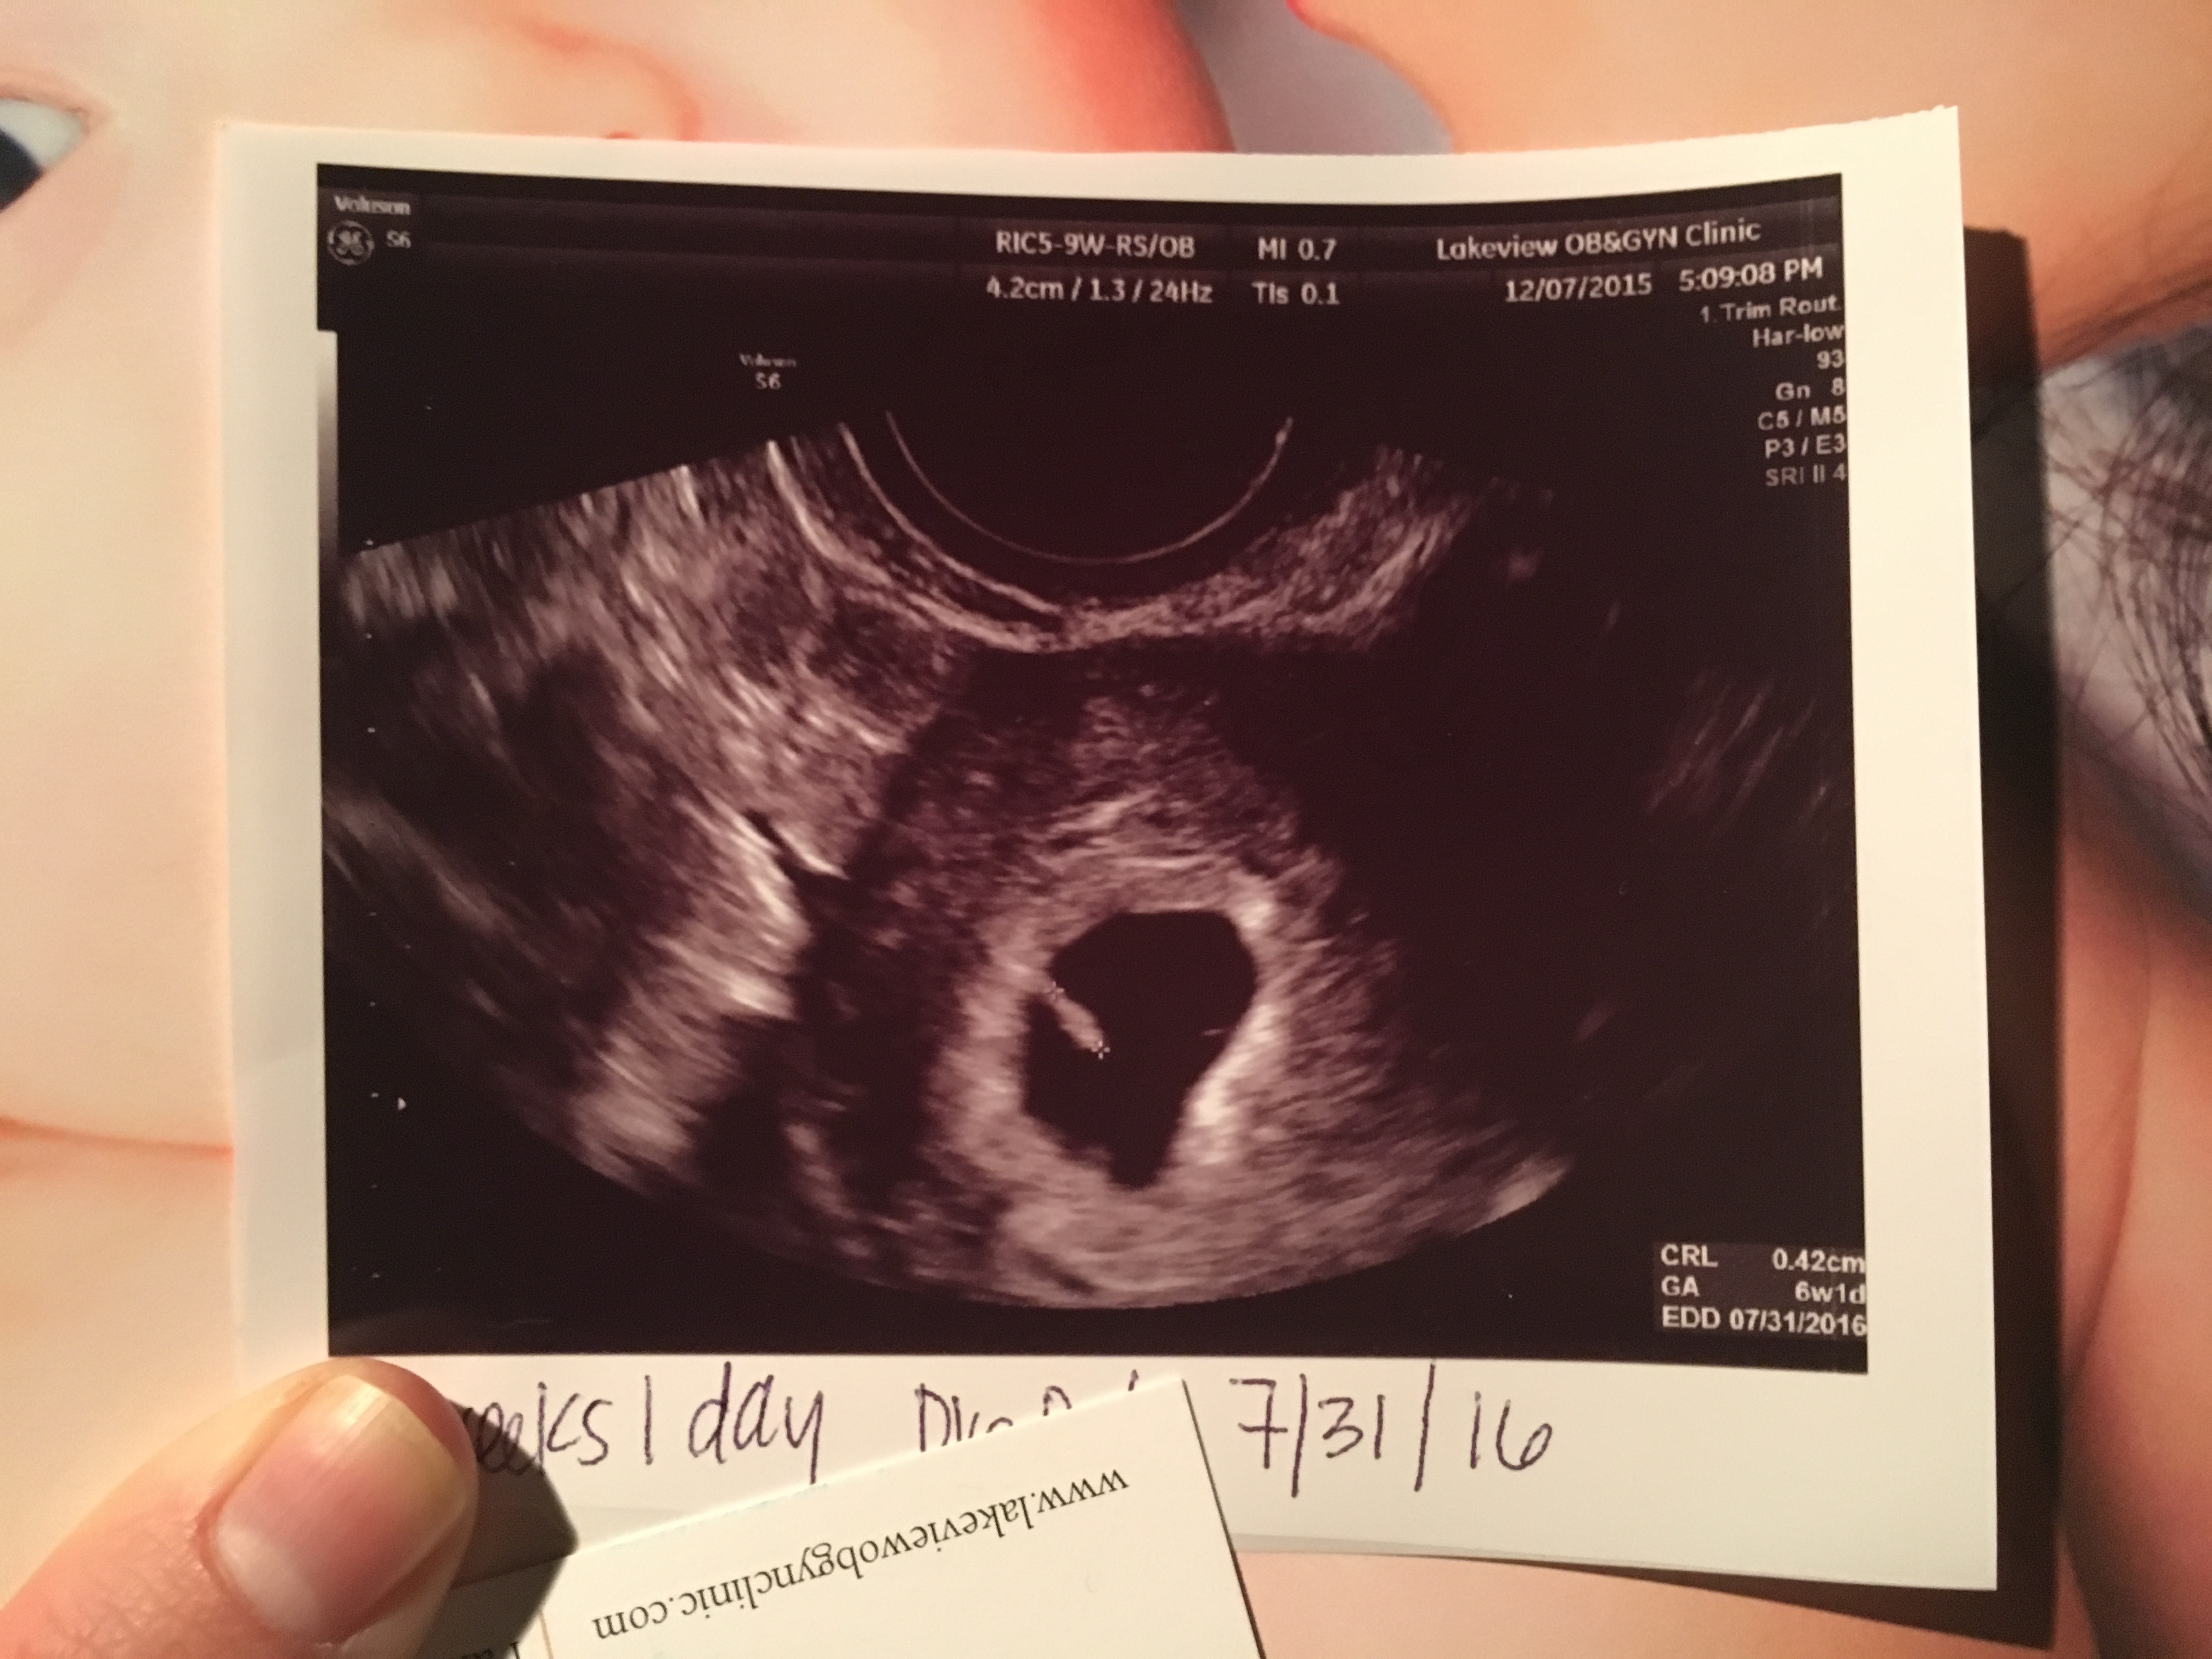

Congrats on all these wonderful pics!! I will probably be bringing up the rear because my EDD is July 31st and my first u/s is the 14th at 7w 1d.....I can't wait.

My first ultrasound pic at 9w3d. Measured a few days small. Doctor pointed out that I had twins, but one was not able to stick around We're sad about this, but we're thrilled to see our other healthy little baby! So in love!